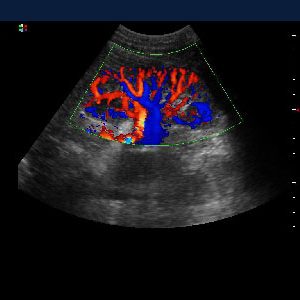

Among its cutting-edge technologies is Colour Doppler, a vital tool in diagnostic imaging. This technique utilizes sound waves to visualize blood flow in real-time, providing crucial information about vascular health and identifying abnormalities. At Lotus Imaging, patients benefit from state-of-the-art Colour Doppler technology, ensuring accurate diagnoses and precise treatments.